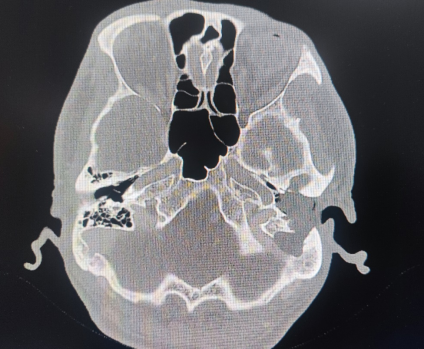

刁先生经过多方打听,找到了西南医科大学附属中医医院耳鼻咽喉科刘强博士。经过耳内镜检查。提示左侧外耳道闭锁,增强CT提示左侧中耳有一个巨大肿物(性质不详)、乙状窦骨壁破坏、面神经管骨质破坏,听力检查结果提示左耳极重度听力损失,但在100分贝时仍有一定的言语识别率。

刘强医生说:“对于该例患者,胆脂瘤破坏了面神经管壁、乙状窦血管壁,导致了外耳道闭锁,已经是胆脂瘤发展到比较严重的程度了。”

术中顺利切除了中耳肿物,并完整保留了乙状窦血管壁,避免了术中大出血;发现面神经垂直段裸露,也得到了很好的保护。对病灶进行了清理后,医生尝试为其安置了人工听小骨假体。由于刁先生外耳道闭锁,医生在清除了闭锁的粘连灶后,又为其扩大了外耳道口,重建了外耳道。术后对肿物进行病理检查,提示为中耳胆脂瘤。